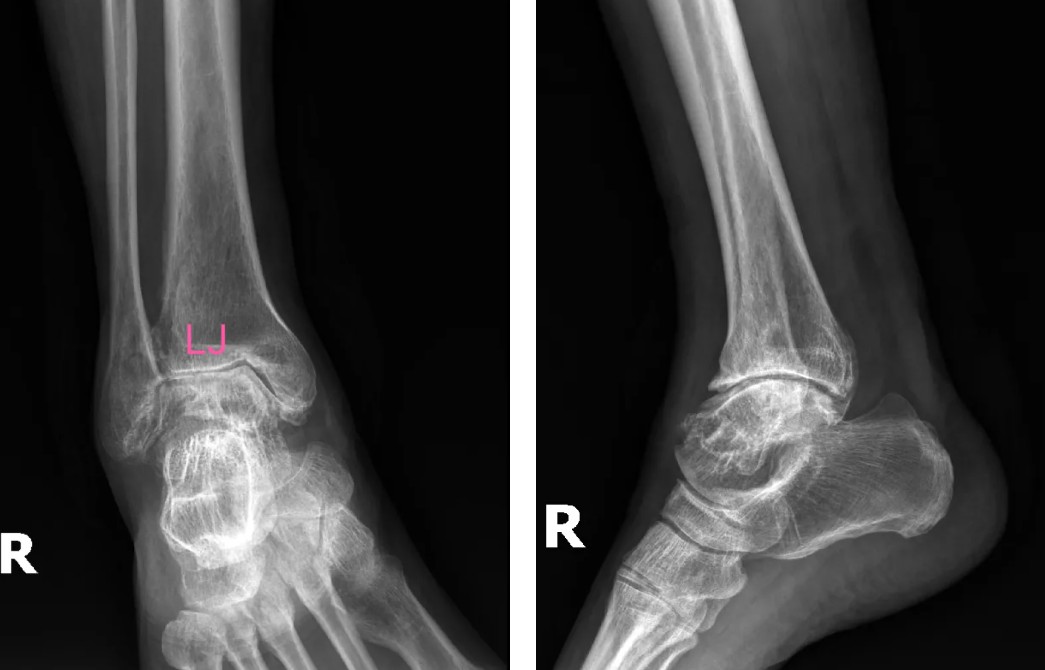

術(shù)前影像

患者吳先生(66歲)雙踝關(guān)節(jié)疼痛、活動(dòng)受限長(zhǎng)達(dá)10余年,保守治療無(wú)效后,關(guān)節(jié)逐漸畸形腫脹,連正常走路都成了奢望。廣安醫(yī)院副院長(zhǎng)、關(guān)節(jié)科主任羅軍副主任醫(yī)師團(tuán)隊(duì)經(jīng)全面評(píng)估,決定采用3D打印定制化人工全踝關(guān)節(jié)置換術(shù)。